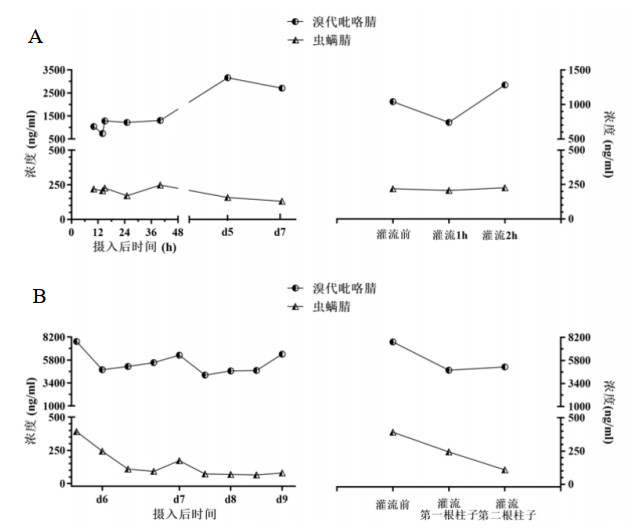

1 资料与方法 1.1 治疗经过病例1是一名70岁男性,因“口服甲维虫螨腈(甲氨基阿维菌素1%,虫螨腈5%)20 mL, 10 h”入院,虫螨腈含量1 g。患者自服杀虫剂5 h后在当地医院予清水500 mL催吐1次。摄入10 h后转至本院,入室查体:T 36.8℃,P 98次/min,R 20次/min,BP 138/83 mmHg,SpO2 97%,心肺腹部均无异常。初步诊断:急性杀虫剂中毒(虫螨腈)。给予乳果糖90 mL、复方聚乙二醇电解质散1 000 mL、20%甘露醇250 mL口服导泻,30%脂肪乳250 mL静脉滴注。摄入毒物后13 h、16 h、38 h、41 h、60 h、63 h共行6次(2次/ d×3 d)血液灌流,动态监测血液中虫螨腈及代谢产物溴代吡咯腈浓度(见图 1A)。摄入毒物后185 h,患者出现一过性体温升高,最高38.0℃(见图 2A),并伴有四肢肌张力增高。第9天患者自动出院,出院后3 d随访无异常,其后失访(通过多种方式未查证到患者死亡信息)。在入室、首次血液灌流1 h、2 h、12 h后,以及灌流3次后、入室第5天、第7天共7个时间点,分别留取EDTA抗凝血2 mL。(住院期间实验室检查见表 1,颅脑影像学检查见图 3A、B)。

| 图 1 入院后病例1(A)和病例2(B)血液中虫螨腈和溴代吡咯腈浓度变化 Fig 1 Changes of blood chlorfenapyr and tralopyril concentrations in case 1 (A) and case 2 (B) after admission |

病例2是一名40岁女性,因“口服虫螨腈虱螨脲(虫螨腈9.5%,虱螨脲2.5%)250 mL 149 h”入院,虫螨腈含量23.75 g。患者自服杀虫剂后家属立即予以催吐1次,摄入毒物后2 h即感全身燥热、多汗。患者拒绝洗胃,当地医院未予特殊治疗。149 h后转至本院,入室查体:T 36.5℃,P 75次/min,R 18次/min,BP 99/67 mmHg,SpO2 98%,神志清楚,心肺腹部均无异常。初步诊断:急性杀虫剂中毒(虫螨腈)。予30%脂肪乳250 mL静脉滴注、血液灌流2次/ d×2 d共4次、持续性血液透析滤过(continuous veno-venous hemodiafiltration, CVVHDF)治疗85 h,动态监测血液中虫螨腈及溴代吡咯腈浓度(见图 1B)。摄入毒物203 h患者出现烦躁、谵妄,230 h转为昏迷状态。237 h患者突发呼吸停止,血压下降至54/36 mmHg,双瞳直径散大至3.5 mm,立即予经口气管插管、机械通气,同时积极抗休克治疗,血压难以维持,患者于摄入247 h后死亡。在入室、首次血液灌流后、第二次灌流后,发病第7、8、9天的6:00和18:00共9个时间点,分别留取EDTA抗凝血2 mL。(住院期间实验室检查见表 1,颅脑影像学检查见图 3C)。

2 结果病例1首次灌流前血虫螨腈浓度为219 ng/mL,溴代吡咯腈浓度为1 041 ng/mL;灌流1 h时,血虫螨腈浓度下降不明显,溴代吡咯腈浓度下降率为28.82%(浓度下降率定义为:灌流前后浓度差与灌流前浓度比值的百分数);灌流2 h时两者均回升并超过灌流前水平。第3次血液灌流(摄入40 h)完成后,血虫螨腈、溴代吡咯腈浓度仍超过首次灌流前浓度,虫螨腈浓度达到检测的最高值248 ng/mL,溴代吡咯腈浓度为1 307 ng/mL。摄入后130 h和178 h血虫螨腈浓度呈下降趋势;血溴代吡咯腈浓度在130 h达峰为3 164 ng/mL,178 h下降至2 707 ng/mL。

病例2首次灌流前血虫螨腈、溴代吡咯腈浓度分别达到392 ng/mL和7 733 ng/mL,首次血液灌流后虫螨腈浓度降至244 ng/mL,下降率为37.75%;溴代吡咯腈浓度降至4 793 ng/mL,下降率为38.02%,其后CVVHDF治疗12 h,血液中虫螨腈及溴代吡咯腈浓度分别反跳至173 ng/mL和6 318 ng/mL,继续给予血液灌流2次,两者浓度下降率分别为58.38%和32.99%。继续CVVHDF治疗85 h,监测血液中虫螨腈浓度维持在69~80 ng/mL,溴代吡咯腈浓度维持在4 234~6 410 ng/mL。

以上两个病例在疾病不同时期接受不同的血液净化方案,病例1在中毒早期给予3 d共6次血液灌流,其血毒物浓度在最初72 h内没有明显的下降,结合其现有的理化特性推测,首先虫螨腈和溴代吡咯腈的Vd可能较大,在其他脏器广泛分布(本课题组已在动物预实验中发现该现象),不断地释放入血。其次胃肠道对于虫螨腈的吸收部位和速度可能具有特殊性,两个因素使得血药浓度长时间处于较高的水平,下降缓慢,代谢产物溴代吡咯腈的浓度下降期出现的更加滞后。对于病例2,在中毒后期(摄入150 h)给予血液灌流4次,基本可去除消化道持续吸收的干扰。每两次血液灌流血溴代吡咯腈浓度下降率为33.67%和32.99%。但后期持续给予CVVHDF,血溴代吡咯腈浓度下降不明显,甚至出现反跳。因此推测:持续性血液透析滤过清除溴代吡咯腈的能力差,这与物质脂溶性、Vd特性相关。在患者肾功能正常的情况下,溴代吡咯腈血浓度无明显变化,提示其从肾脏代谢量较少。在病程后期给予CVVHDF可以控制体温、稳定内环境,但对减轻脑水肿、挽救生命并无明显作用。其他血液净化方式如血浆置换,对虫螨腈及溴代吡咯腈的清除效果仍需进一步研究评估。

对比两个病例的发病经过、血液净化处方、血药浓度曲线以及虫螨腈和代谢产物溴代吡咯腈的LD50, 笔者认为:患者的预后与摄入量、是否早期进行血液灌流和血液灌流的频次、后期血液中溴代吡咯腈的浓度相关。血液中溴代吡咯腈的浓度可能是较好的患者预后指标。以上的想法仍需要更多的数据进行验证。